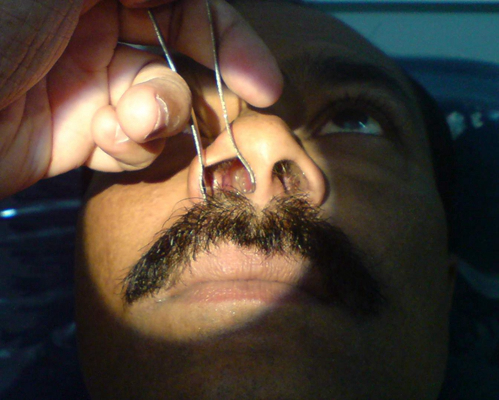

鼻竇炎圖片